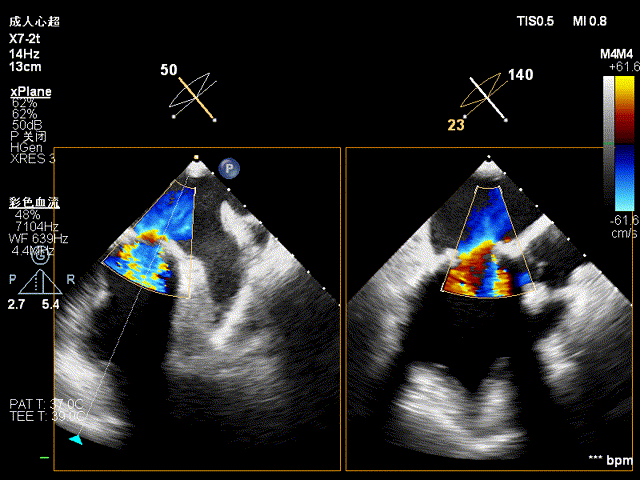

术前超声显示主动脉瓣大量反流:

即刻复查食道超声,长轴切面显示瓣架深度合适,瓣叶启闭正常,未见明显瓣周漏: